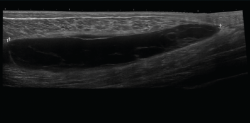

Ecografía

El ultrasonido se puede usar en el diagnóstico de numerosas patologías y puede guiar en procedimientos diagnósticos y terapéuticos(5).

Su indicación fundamental es en el diagnóstico de las lesiones de partes blandas superficiales.

Las estructuras específicas más adecuadas para este estudio incluyen tendones, músculos y ligamentos, además de masas periarticulares de tejidos blandos. Es útil para el diagnóstico de derrame articular, engrosamiento sinovial, bursitis, cuerpos libres intraarticulares, gangliones, quistes, roturas ligamentosas y tendinosas, tendinitis y fracturas ocultas(6).

En el estudio musculoesquelético se utiliza una sonda lineal con alta frecuencia, de entre 9 y 13 mHz.

2. Tendones

2.1. Tendinitis

Con ecografía Doppler pueden aparecer áreas de hiperemia intratendinosa o peritendinosa (Figura 8).

Figura 8. Corte sagital de una ecografía de rodilla del tendón rotuliano: engrosamiento del tendón con aumento difuso de ecogenicidad.

2.2. Roturas

Se observan áreas hipoecoicas de solución de continuidad de las fibras tendinosas(7), con retracción de los márgenes con la contracción muscular cuando la rotura tendinosa es completa (Figuras 9 y 10).